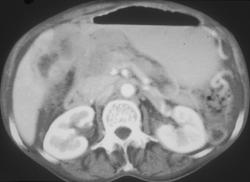

Severe Gastritis and Portal Vein Thrombosis